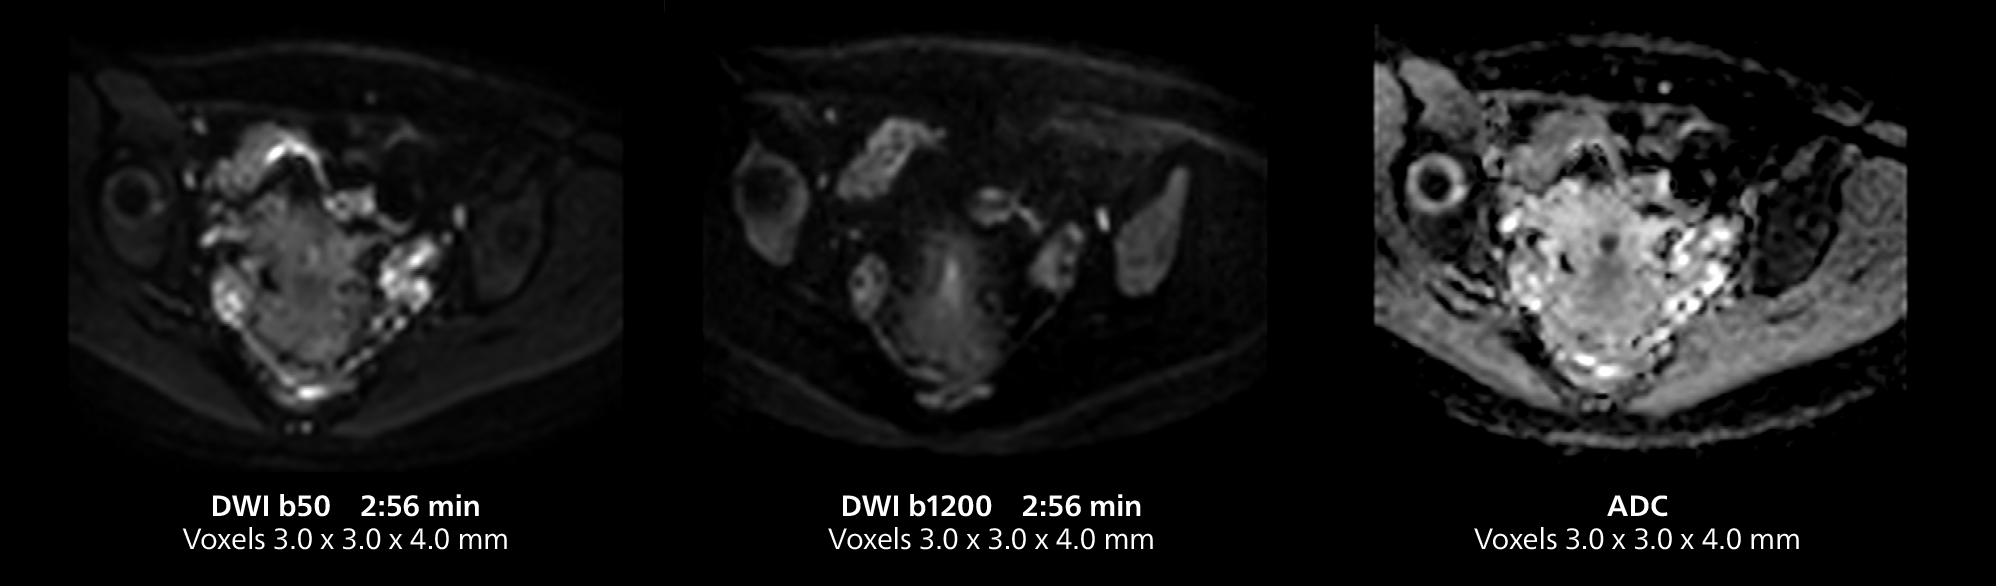

The isotropic high resolution 3D sequence in this MRI case allows for reformatting to obtain other orientations with high quality. Acquired on the MR 5300 system.

Dr. Gellée highlights the robust free-breathing scans as “the feature that makes the biggest difference in my daily work. The 3D free breathing sequences are very reproducible, and the axial acquisition is very good. For example, in endometriosis, which is one of my focus areas, it provides high contrast and good resolution so that I can see small details. We also use free breathing for liver and pancreas imaging. In multi-phase liver studies, 4D Free Breathing delivers 3-second temporal resolution, making a dynamic scan with more than one arterial phase possible.”

The MR 5300 with Compressed SENSE is up to 50%** faster for many exams. It can provide routine exams in less than 5 minutes and whole-body exams in less than 20 minutes. Saint-Augustin has taken advantage of that speed to create highly efficient protocols. The hospital’s standard stroke protocol is just about 8 minutes, and standard ENT, prostate PIRADS staging, and endometriosis studies all clock in at just about 10 minutes.***

“We have more speed in 3D sequences,” Dr. Gellée states. “With Compressed SENSE, we can replace two or three 2D scans withone high-quality 3D scan. High quality additional orientations are then obtained by post-processing of the 3D data set, thus saving scanning time.”